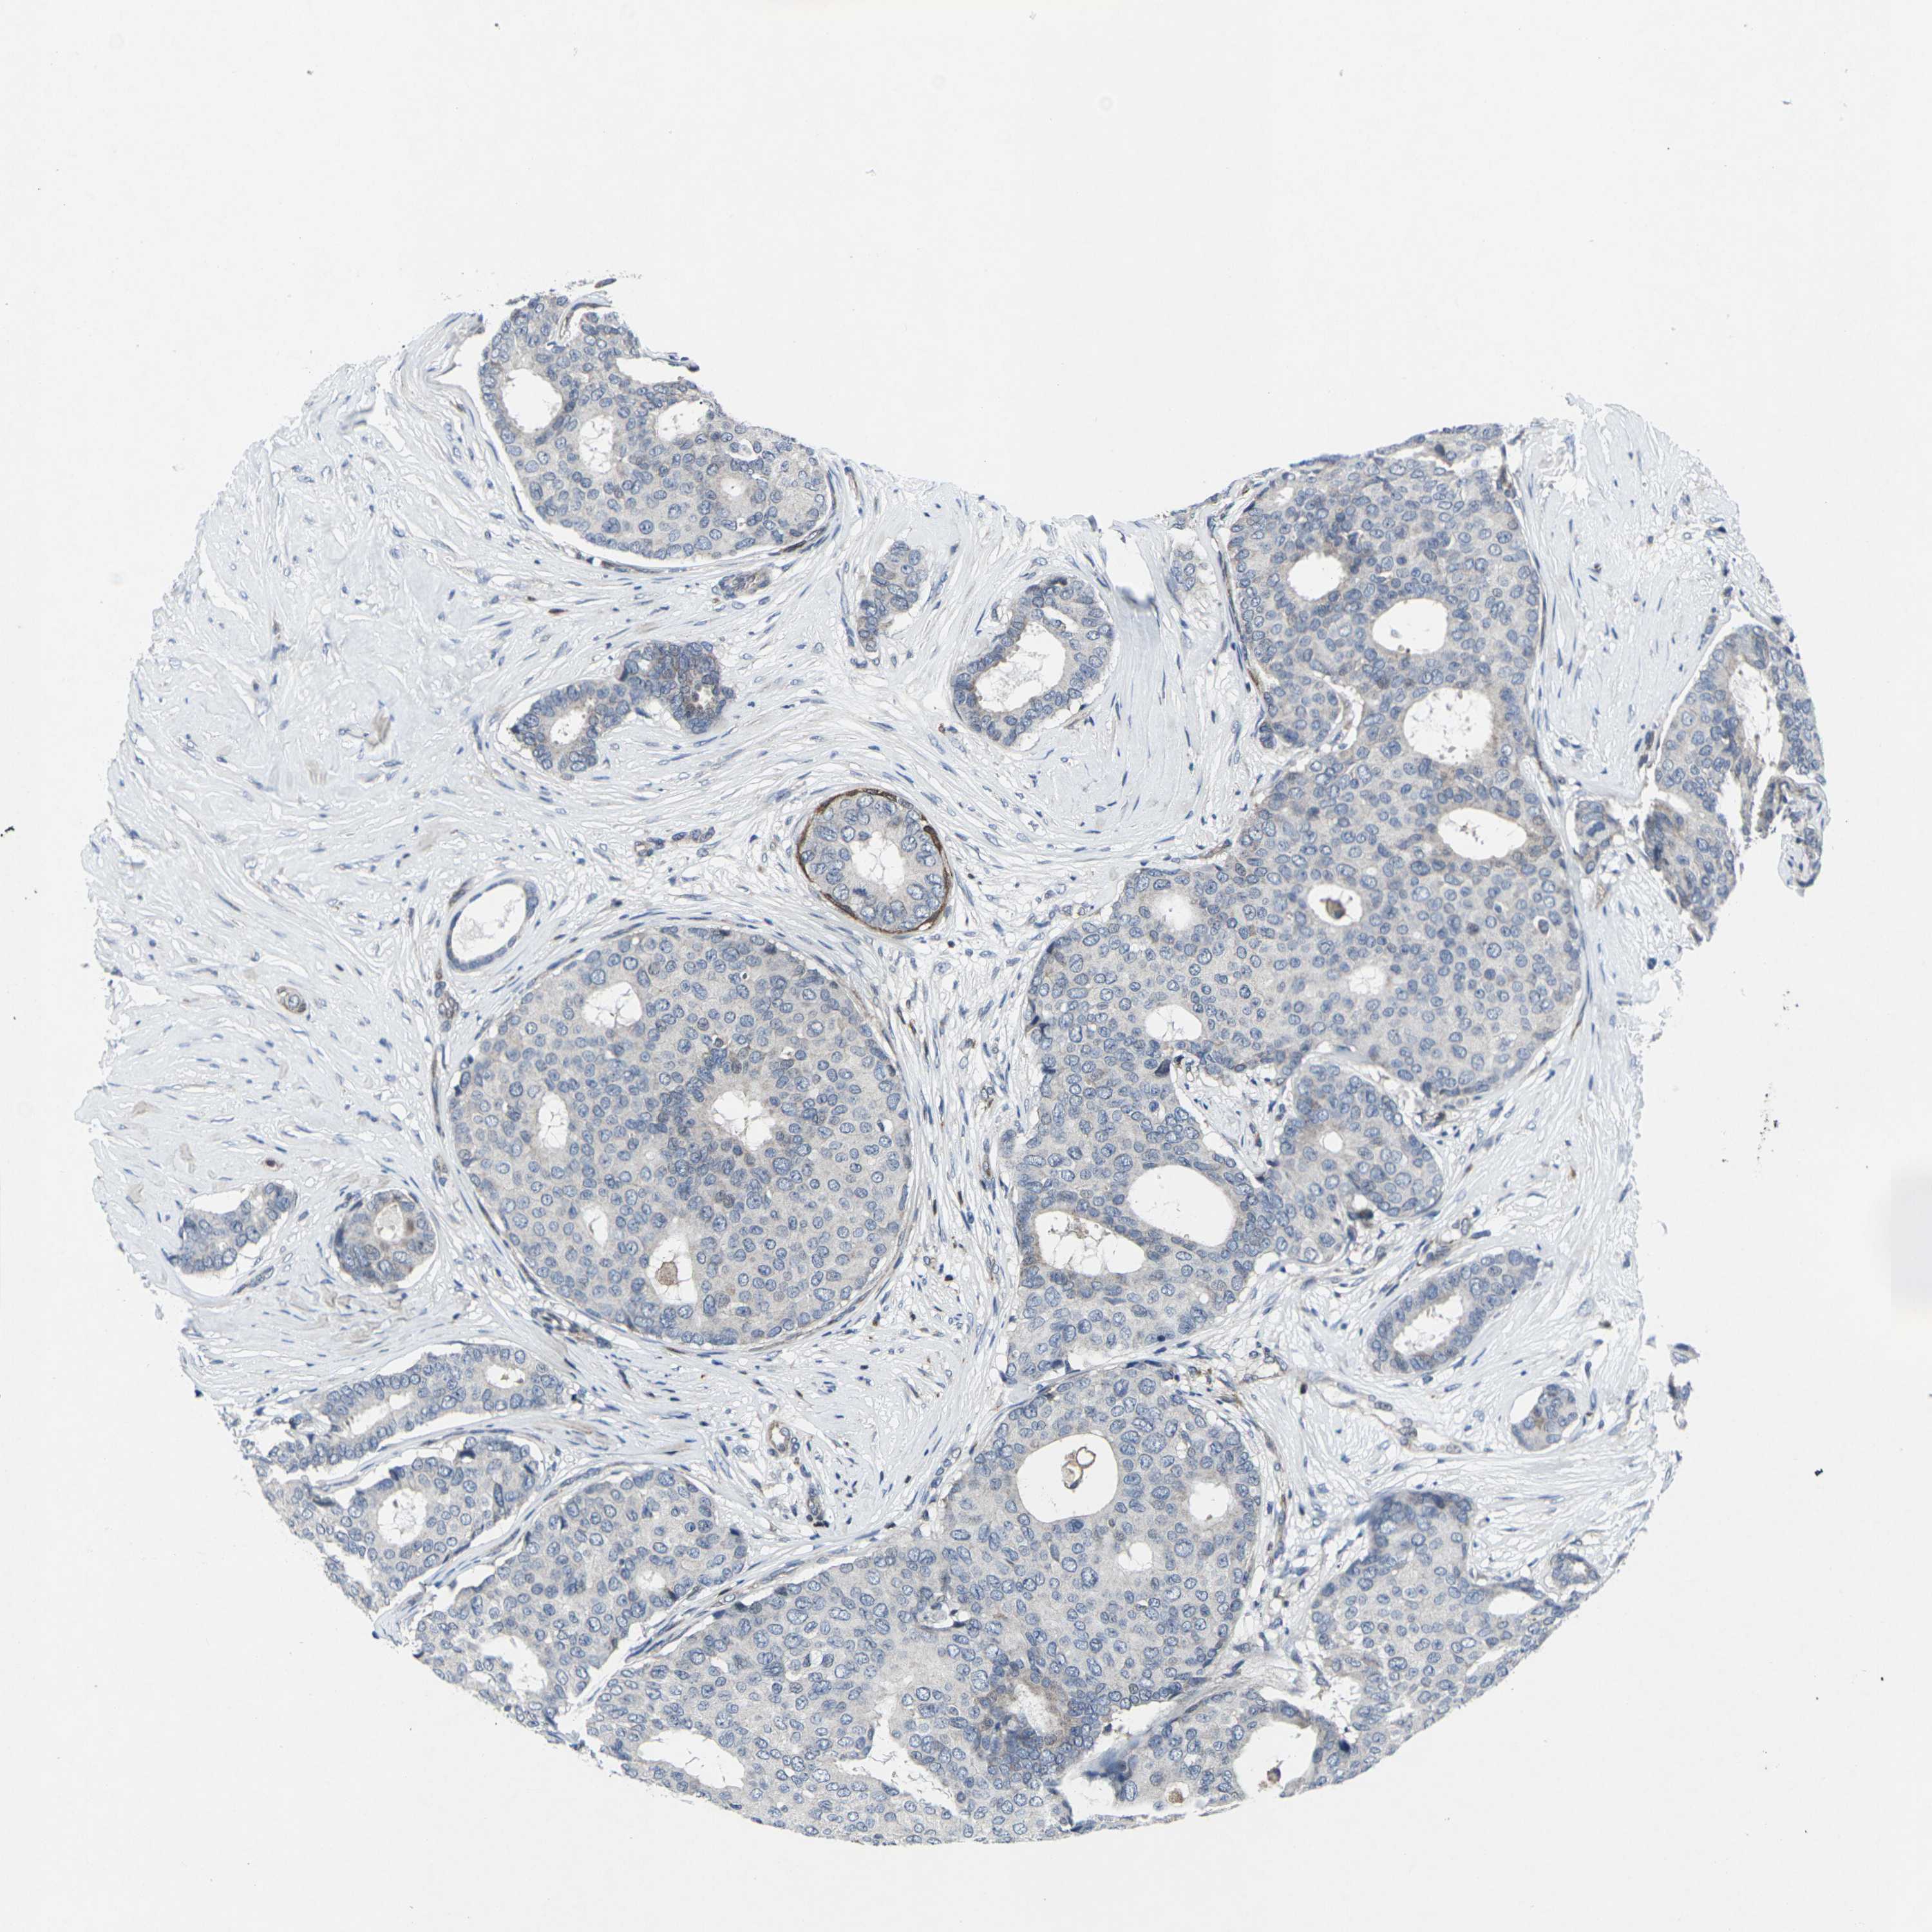

CANCER BREAST CANCER Show tissue menu

BRCA TCGA BRCA VALIDATION PROTEIN EXPRESSION